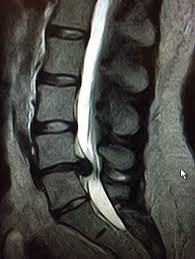

Bandscheibenvorfall In Der Lws Erkennen Und Behandeln Das Musst Du Wissen Bandscheibenvorfall Bandscheiben Bandscheibenvorfall Ubungen